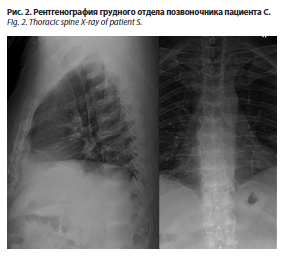

На рентгенограммах грудного отдела позвоночника в прямой и боковой проекциях (рис. 2) травматических изменений не выявлено. Физиологический грудной кифоз сохранен. Ось отдела отклонена вправо (угол сколиоза 7° по Коббу на вершине ThVIII). Межпозвонковые пространства снижены, кортикальные пластинки тел позвонков склерозированы, утолщены, определяются зоны уплотнения от межпозвонковых пространств (кальцификация?). Тела позвонков равномерные по высоте (на высоте кифоза определяется снижение высоты тел позвонков в передних отелах, больше данных, свидетельствующих о дистрофических изменениях). По передним и боковым краям тел позвонков – краевые остеофиты. Определяются сужение суставных щелей дугоотростчатых суставов, склероз субхондральных отделов. Заключение: рентгенологическая картина дегенеративно-дистрофических изменений грудного отдела позвоночника. Спондилез. Сколиоз. Спондилоартроз. Хондрокальциноз?

На рентгенограммах грудного отдела позвоночника в прямой и боковой проекциях (рис. 2) травматических изменений не выявлено. Физиологический грудной кифоз сохранен. Ось отдела отклонена вправо (угол сколиоза 7° по Коббу на вершине ThVIII). Межпозвонковые пространства снижены, кортикальные пластинки тел позвонков склерозированы, утолщены, определяются зоны уплотнения от межпозвонковых пространств (кальцификация?). Тела позвонков равномерные по высоте (на высоте кифоза определяется снижение высоты тел позвонков в передних отелах, больше данных, свидетельствующих о дистрофических изменениях). По передним и боковым краям тел позвонков – краевые остеофиты. Определяются сужение суставных щелей дугоотростчатых суставов, склероз субхондральных отделов. Заключение: рентгенологическая картина дегенеративно-дистрофических изменений грудного отдела позвоночника. Спондилез. Сколиоз. Спондилоартроз. Хондрокальциноз?На рентгенограммах пояснично-крестцового отдела позвоночника в прямой и боковой проекциях (рис. 3) травматических изменений не выявлено. Физиологический лордоз сглажен. Ось отдела незначительно отклонена влево. Межпозвонковые пространства снижены, кортикальные пластинки тел позвонков склерозированы, утолщены, определяются зоны уплотнения от межпозвонковых пространств (кальцификация?). Тела позвонков равномерные по высоте. По передним и боковым краям тел позвонков – краевые остеофиты. Определяются сужение суставных щелей дугоотростчатых суставов, склероз субхондральных отделов. Заключение: рентгенологическая картина дегенеративно-дистрофических изменений грудного отдела позвоночника. Спондилез. Сколиоз. Спондилоартроз. Хондрокальциноз?